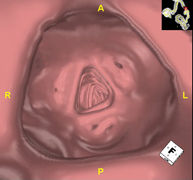

- Broncoscopia virtual La broncoscopia virtual es una técnica no invasiva que permite la visualización tridimensional y bidimensional de la tráquea y del árbol bronquial mediante la toma secuencial de imágenes captadas con TC Multidetector, obteniendo imágenes bi y tridimensionales. La calidad de las imágenes permite la navegación virtual por el interior de la tráquea y de los bronquios gracias al procesamiento en estaciones de trabajo especializadas. La broncoscopia virtual es una técnica no invasiva que permite la visualización tridimensional y bidimensional de la tráquea y del árbol bronquial mediante la toma secuencial de imágenes captadas con TC Multidetector, obteniendo imágenes bi y tridimensionales. La calidad de las imágenes permite la navegación virtual por el interior de la tráquea y de los bronquios gracias al procesamiento en estaciones de trabajo especializadas.

- Colonoscopia virtual  La colonoscopia virtual es una técnica no invasiva que permite la visualización tridimensional y bidimensional del intestino grueso o del colon mediante la toma secuencial de imágenes captadas con TC Multidetector de última generación. La calidad de las imágenes permite la navegación virtual por el interior del recto y del colon gracias al procesamiento en estaciones de trabajo especializadas. La preparación de la prueba consiste en realizar una dieta baja en fibra tres días antes de la prueba (para limpiar el colon y el recto) y de la ingestión de contraste oral yodado el día antes de la prueba (para marcar las heces y poder distinguirlas correctamente de las posibles lesiones colónicas). A diferencia de la fibrocolonoscopia, no se requiere sedación ni soluciones evacuantes. La prueba se realiza en la sala del TC donde, a través de un pequeño tubo flexible, se insufla aire para distender el colon. La colonoscopia virtual es una técnica no invasiva que permite la visualización tridimensional y bidimensional del intestino grueso o del colon mediante la toma secuencial de imágenes captadas con TC Multidetector de última generación. La calidad de las imágenes permite la navegación virtual por el interior del recto y del colon gracias al procesamiento en estaciones de trabajo especializadas. La preparación de la prueba consiste en realizar una dieta baja en fibra tres días antes de la prueba (para limpiar el colon y el recto) y de la ingestión de contraste oral yodado el día antes de la prueba (para marcar las heces y poder distinguirlas correctamente de las posibles lesiones colónicas). A diferencia de la fibrocolonoscopia, no se requiere sedación ni soluciones evacuantes. La prueba se realiza en la sala del TC donde, a través de un pequeño tubo flexible, se insufla aire para distender el colon.